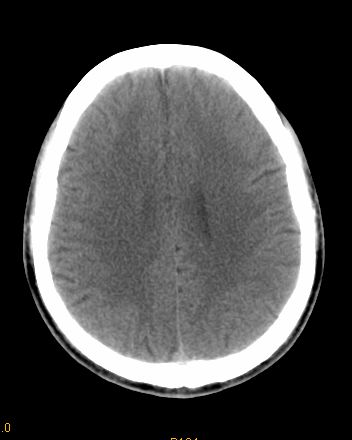

男 42岁 头痛20天

左顶叶见片状低密度影,边界不清,内见斑片状等密度影。考虑转移性肿瘤可能性大,建议ct增强或mr增强扫描。建议胸部检查,排除肺部病变。

左顶叶见片状低密度影,内似见结节状略高密度影,建议增强扫描。

左侧顶叶低密度灶,性质待定;建议行ct增强扫描或mri检查。

左顶叶见片状低密度影,边界不清,内见斑片状等密度影。考虑转移性肿瘤可能性大,建议ct增强或mr增强扫描。建议胸部检查,排除肺部周围型腺癌。